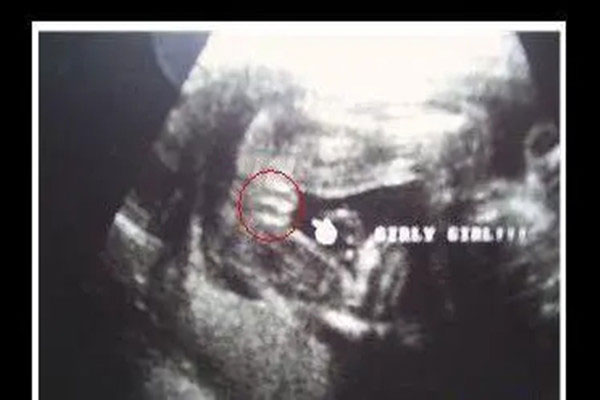

女宝b超三条线是哪三条,想要生女宝的孕妈一起来看看

女宝b超三条线是哪三条 自从怀孕以后,总是想知道肚子里怀的是男孩还是女孩。很多二胎想要生女宝的孕妈妈,你们一定听说过,怀女孩的话前期孕吐比较厉害;又或者说是怀女孩..